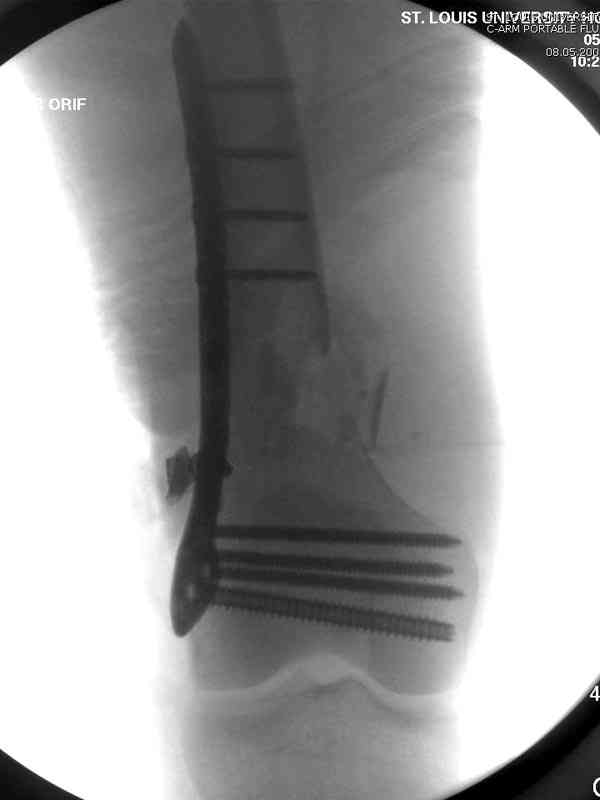

Пострадавшему 23, пистолетная огнестрельная не кроветочащая рана, меньше одного см диаметром, входное отверстие расположено латерально, и выход передне-медиально, и еще имеется второе пулевое ранение правой navicular bone с этой стороны.

Доступ был латеральный, при вскрытии с задней

поверхности бедра обнаружили кровотечение. Поднятием давления на заранее установленном турникете на конечности проконтролировали кровотечение.

В данном случае мы не ставили осуществление гемостаза приоритетным, после 30 минут больной оставлен вызванному сосудистому хирургу со стабильной фиксацией бедра. Несмотря на выбранный передне-медиальный доступ, хирург произвел восстановление сосудистого повреждения.

Латерально пластину защитили ушиванием

илио-тибиального тракта, а медиальная сторона была ушита мышцей, и все раны закрыли ваккумированием (VAC)

На третий день после Irrigation & Debridment закрыли все раны за исключением компартментальной раны из-за отека, медиально в дефект кости установили Putty Grafton Bone Substitute. На компартментальную рану вакуум и мероприятия по сближению краев раны резиновой стяжкой.

На 9й день с момента травмы ушили рану без натяжения. Больной получает реабилитацию, движения коленного сустава с помощи CPM-continuous passive motion machine. Сегодня выписан.